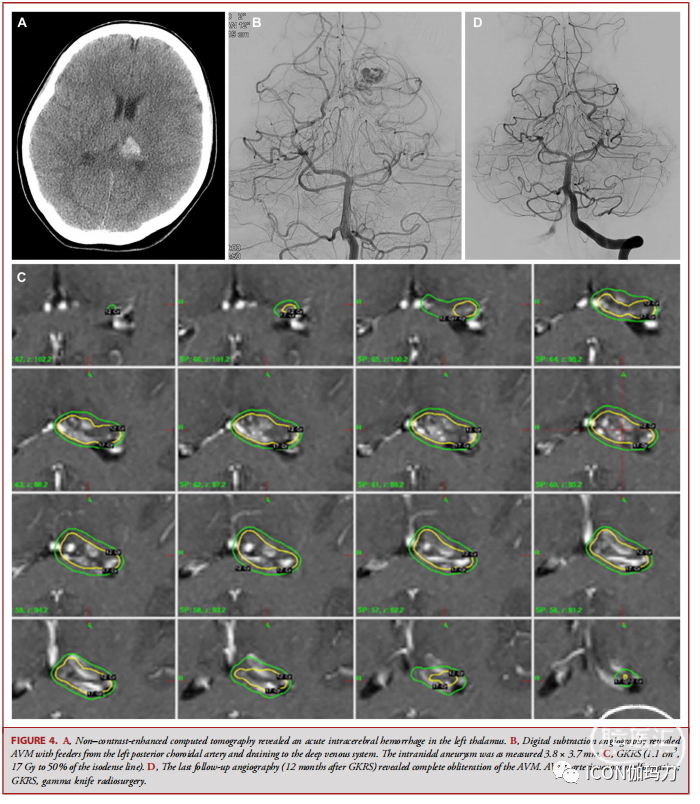

患者突然出现右侧无力。平扫计算机断层扫描显示左侧丘脑急性脑出血(图4A)。DSA显示左侧脉络膜后动脉供血,并引流至深静脉系统。颅内动脉瘤大小为3.8 × 3.7 mm(图4B)。5 d后行GKRS 治疗(1.1 cm3, 17 Gy ,50%等信号线;图4 c)。GKRS治疗后5 d,患者接受了25%氰基丙烯酸正丁酯栓塞术。影像学随访时(GKRS治疗后12个月),DSA显示AVM完全闭塞(图4D)。

图4。A,无对比增强计算机断层扫描显示左侧丘脑急性脑出血。B,数字减影血管造影显示AVM,其供血动脉来自左侧脉络膜后动脉并引流至深静脉系统。动脉瘤直径3.8 × 3.7 mm。C: GKRS (1.1 cm3, 按50%等剂量线,17 Gy)。D, GKRS治疗后12个月复查血管造影显示AVM完全闭塞。AVM,动静脉畸形;GKRS,伽玛刀放射外科。